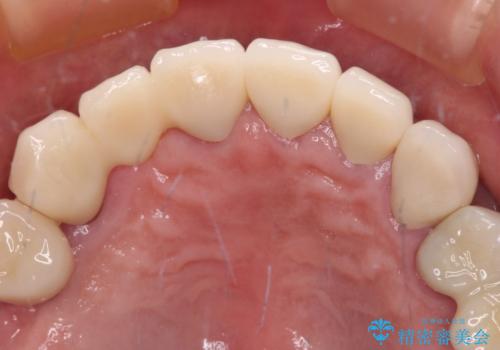

前歯部については抜歯が必要な歯を抜歯し、インプラントやブリッジなどにより補綴治療を行うこととしました。

臼歯部は今後抜歯が必要となった際に、インプラントにより咬合を構築していくこととしました。今回の治療においても、今後の臼歯部の治療に対応できるよう治療計画を立案しています。